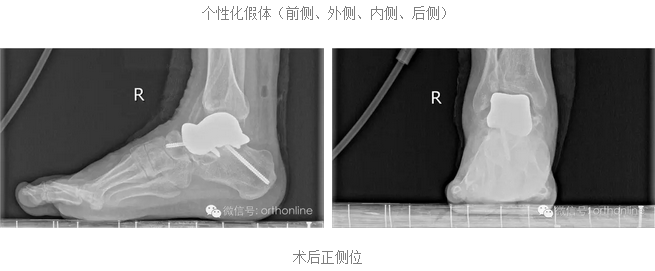

除了具有3D打印构建的支撑作用外,还对假体进行了结构差异化设计,具有更为优质的结构承重功能;

假体关节面材料经过特殊处理,除了关节接触耦合好、摩擦小等特点,更重要的是假体的弹性模量与人体更为接近,大大提高了耐磨性;

突破传统的3D打印假体的界面处理方法,采用假体界面微孔打印等方法,更有利于骨组织长入。

假体个性化特性更为明显:

假体制作完全忠实于患者个体的解剖结构,术前将健侧的骨性解剖数据进行镜像处理,获得个性化假体数据源;3D打印完成后再将假体扫描,与数据源进行耦合对照检测;假体植入后扫描患肢,检测与数据源耦合性能;

塌陷性距骨坏死一直是踝关节假体置换的绝对禁忌症,该假体打破了常规,为塌陷性距骨坏死提供了非常好的选择。